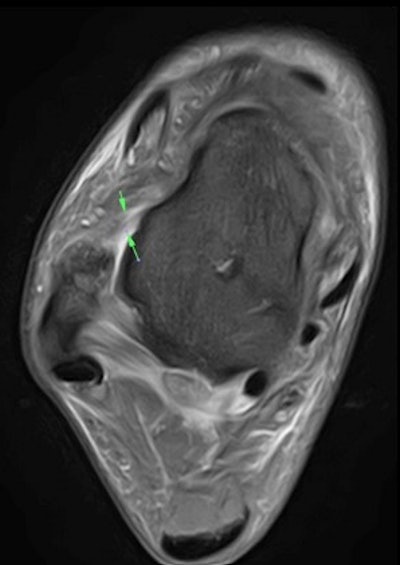

By using a Canon Medical Vantage Galan 3-tesla MRI scanner, we can see the extent of commonly occurring or unique injury onsite within the dedicated Medical Imaging Centre at the Manchester United Carrington Training Centre without any of the confidentiality issues of transferring a patient to a local hospital.

The figure below, for example, shows a T2-weighted image of the coronal view of the right knee. The female athlete has an acute pivot-shift injury with an acute lateral condylar bone contusion, which is highly indicative of an associated ACL tear.

The known predisposition in female footballers has no singular cause, but it is thought to be a mixture of anatomical differences, including the intercondylar notch, a groove at the bottom of the femur where it meets the knee, which is larger in men than in women; increased knee valgus, the Q angle formed between the quadricep muscles and the patella tendon; hip-width differences affecting knee alignment; gender biomechanics, such as joint flexibility, hormones, and menstrual cycles; plus potentially gender differences in early football training.